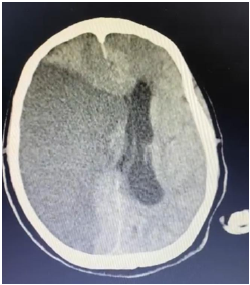

Um paciente de 76 anos de idade deu entrada na UPA, já fora de janela para trombólise, e foi posteriormente encaminhado para a UTI. A imagem apresentada refere-se à tomografia de admissão na UTI.

Diagnosticada a hipertensão intracraniana, a conduta mais prontamente adequada seria o uso de

Na UTI, o paciente evoluiu com aumento progressivo dos níveis pressóricos e com bradicardia.

Qual seria o exame mais facilmente disponível nesse momento, para tentar estabelecer um diagnóstico?

O paciente evoluiu com morte encefálica. O primeiro exame clínico confirmatório foi realizado às 12 horas, o segundo às 13 horas, e o método gráfico às 23 horas. Sabendo que todos os trâmites legais foram feitos, como notificação compulsória e acompanhamento com a ajuda da comissão intra-hospitalar de doação de órgãos e tecidos (CIHDOTT), qual o horário do óbito e qual a medida esperada?

Supondo que o paciente tenha evoluído com a necessidade de craniectomia descompressiva, e já há mais de 5 dias sem uso de drogas sedativas ou analgésicas, qual seria o método gráfico preferencial para a confirmação da morte encefálica para o referido paciente?